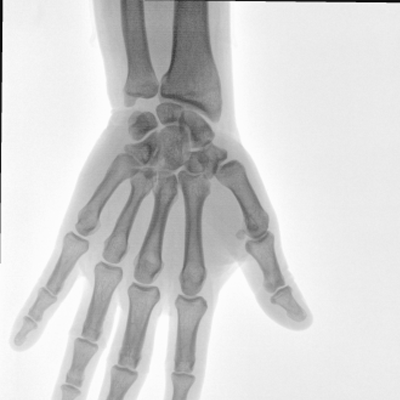

大尺寸動態(tài)平板探測器,高DQE、低噪聲、圖像清晰。采用多分辨率圖像增強(qiáng)處理技術(shù),不同部位不同圖像處理算法,滿足客戶多樣化的需求。